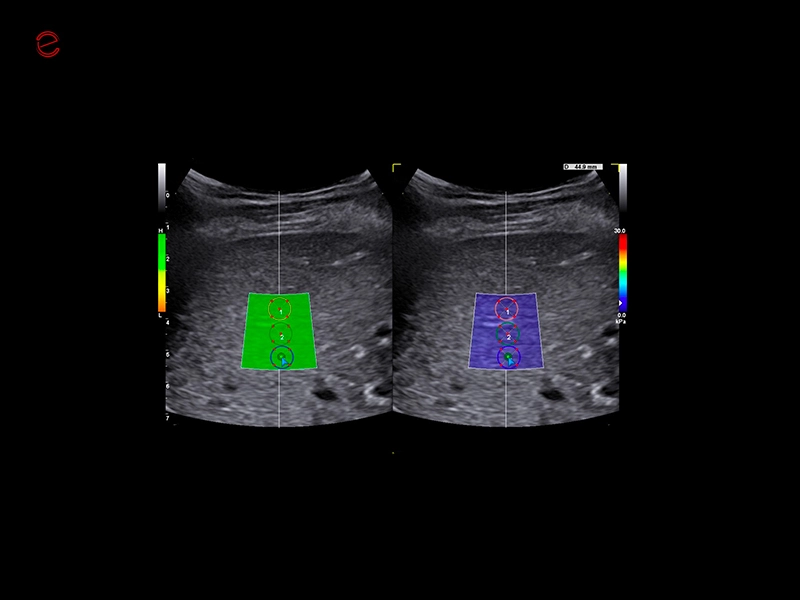

MyLab™9 Platform - QElaXto point Shearwave Elastography in liver

MyLab™9 Platform - QElaXto point Shearwave Elastography in liver

MyLab™9 Platform - QElaXto 2D shearwave elastography in liver

MyLab™9 Platform - QElaXto 2D shearwave elastography in liver